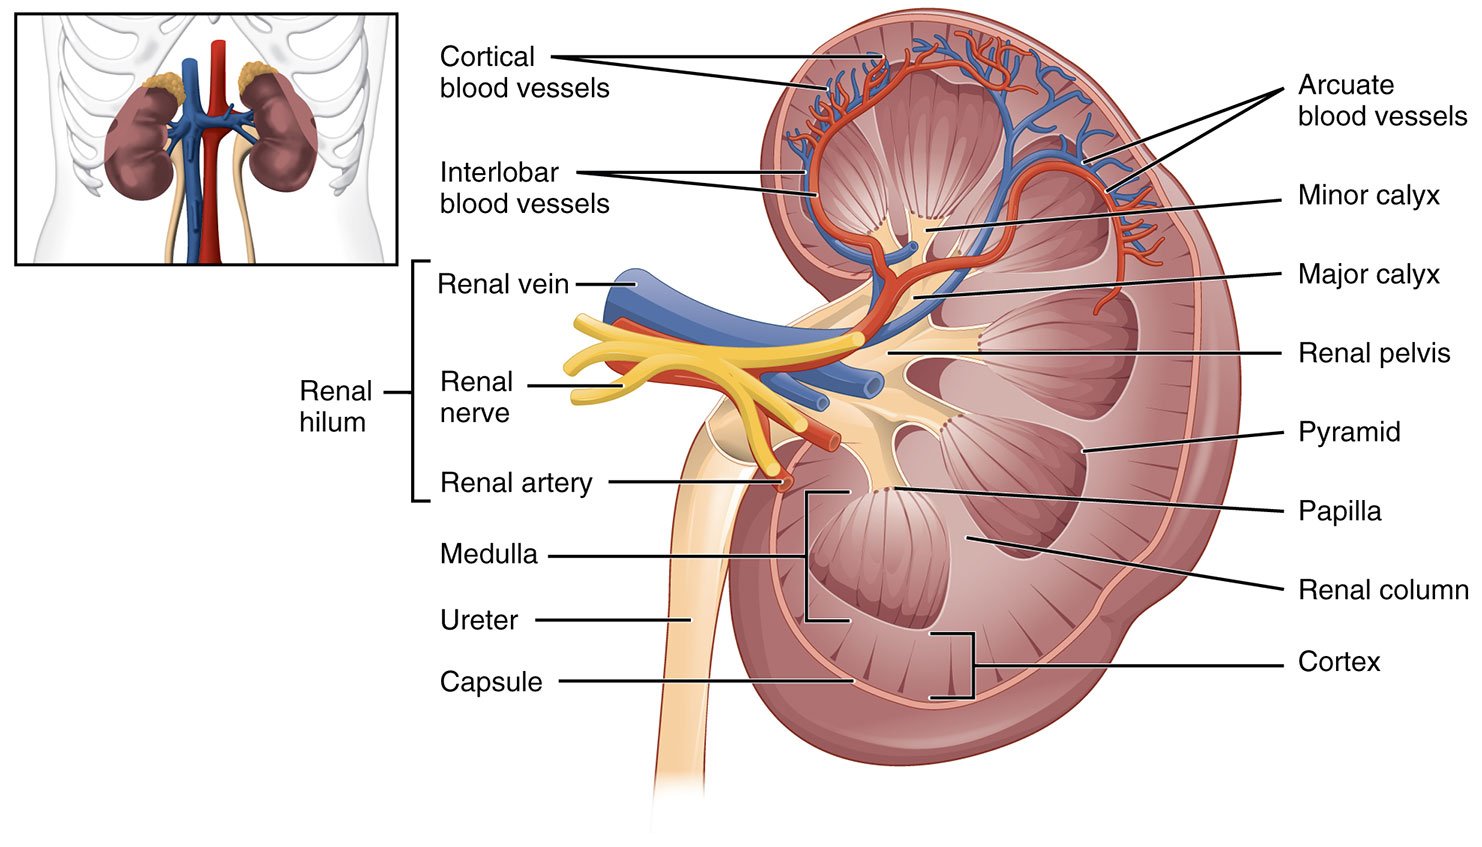

II. Anatomy

- The kidneys are retroperitoneal organs that are protected by the lower ribs posteriorly. The right kidney lies just below the liver, while the left lies just below the spleen. The superior pole of each kidney is tilted slightly medially and posteriorly (oblique lie).

- Grossly, each kidney consists of (from periphery inward):

- Fibrous capsule that supports and protects kidney

- Outer cortex

- Inner medulla containing 6-8 renal pyramids and surrounding columns of cortical tissue.

- Renal sinus, a central cavity on the medial aspect of each kidney which primarily houses the calyces and renal pelvis which collect urine produced in the renal pyramids, but also contains renal sinus fat, branching blood vessels, lymphatics and nerves.

- Renal hilum, which is the entrance/exit for the renal pelvis, blood vessels, lymphatics, and nerves.

- Illustration 1. Normal renal anatomy (Source: https://commons.wikimedia.org/wiki/File:2610_The_Kidney.jpg)

- The whole renal complex is surrounded by a fascial layer, called Gerota’s fascia.